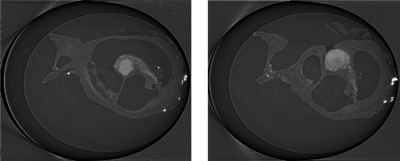

Mouse cochlea tissue samples were scanned at Advanced Photon Source (Argonne National Laboratory, Argonne, IL). The images were then converted to binary and cleaned of noise via Fiji imaging software. The scala tympani at each cross-section was isolated to create an image stack that was used to construct a 3D surface. The surface was then exported to Autodesk Meshmixer (AUTODESK, San Rafael, CA) for modifications.